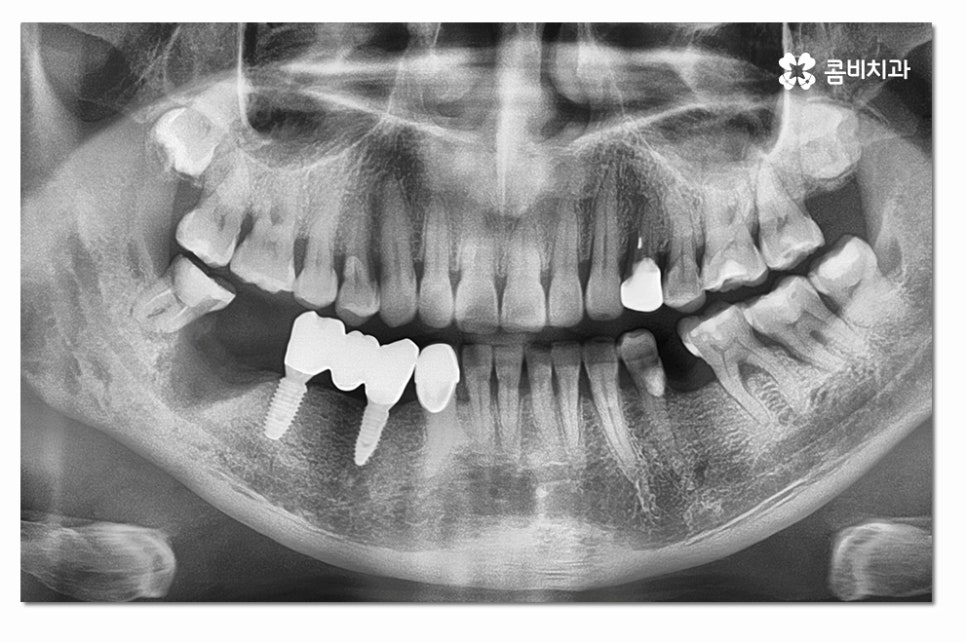

위 사진처럼 어금니를 발치한 후에는 잇몸이 차오르길

기다리게 되고 임플란트를 식립할 잇몸 뼈가

충분한지 잇몸 상태를 정밀 검진을 통해 확인하는 과정을

거치며 잇몸이 부족한 경우에는 뼈이식을 받아야 할 수 있어요.

어금니임플란트의 경우 심미성보다는 기능성에 보다 집중된

치료가 이뤄지게 되는데 요즘은 3D CT 등을 통해

정확도 높은 진단이 이뤄지고 있지만 시술은 의사의 경험과

실력이 중요한 부분이기 때문에 어금니임플란트는

특히 저작기능을 수행하는 데 유리한 식립 각도와

위치 선정을 잘하는 것이 중요하다고 할 수 있어요.